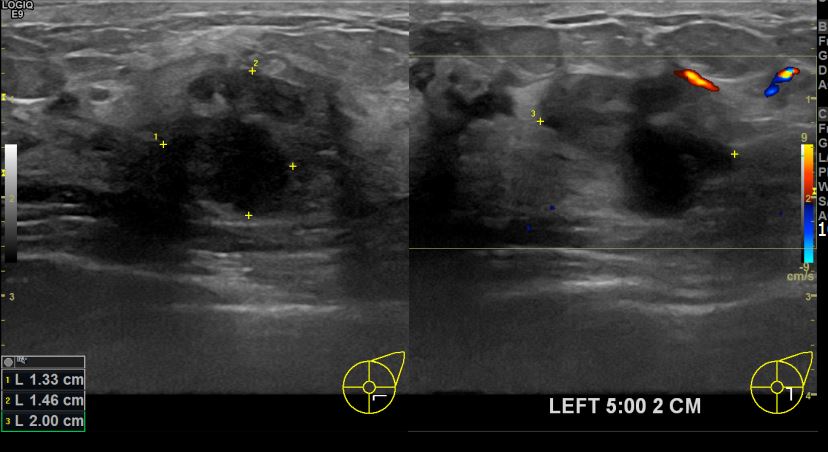

아산유외과개원후 704번째 유방암진단

상기환자 좌측유방멍울만져져 내원하신 40대 여성분으로 유방암의심혹 조직검사 시행 후 유방암 진단되었습니다.